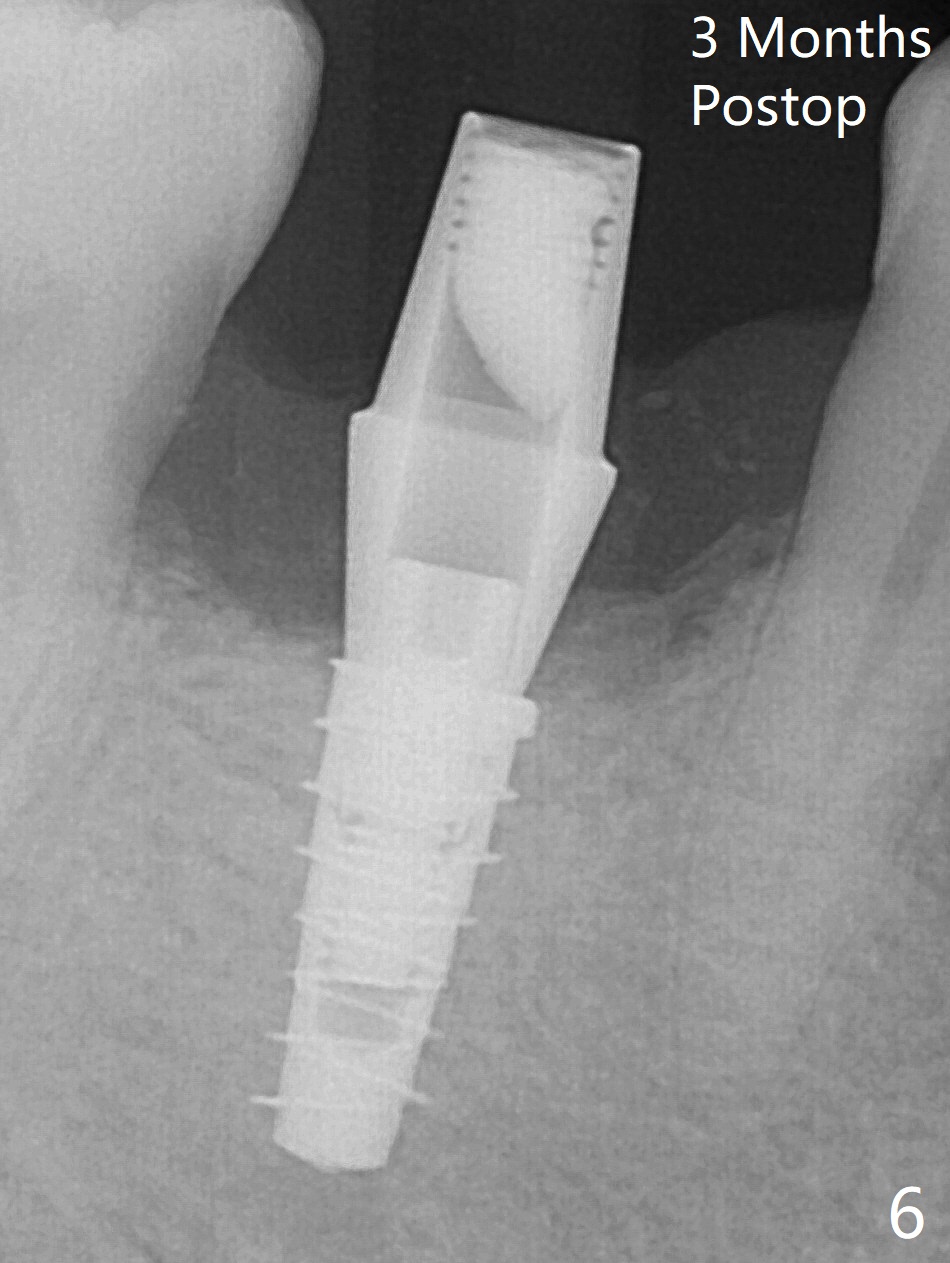

The retained deciduous tooth (lower right 2nd molar, Fig.1 T) has buccal apical infection and recession. After extraction, the initial depth of osteotomy is 11 mm over the flat socket bottom (Fig.2) without visible Mental Loop. Following 3.8 mm Magic Drill for 11 mm, a 4x11 mm dummy implant is placed partially due to hard bone; it appears that the apical osteotomy (Fig.3 yellow outline) overlaps the Mental Loop (red dashed line). For safety, a 4x9 mm IBS implant is placed with insertion torque 40 Ncm; a 5x5.7(4) mm abutment is immediately placed for an immediate provisional to cover the large socket and keep Vera graft in place (Fig.4 *). There is no postop paresthesia, probably due to the fact that the osteotomy is lingual to the Mental Loop. The provisional remains in place 7 days postop; its margin (Fig.5 arrow) covers the socket. The margin of the provisional is trimmed 1 month postop. Impression is taken nearly 3 months postop (Fig.6). The buccal plate looks atrophic 3 months postop (Fig.7 (immediately before cementation)), although there is no sign of periimplantitis. In the future, insert the immediate provisional inside of the buccal gingiva to make the buccal gingiva look bulky instead of buccal to it (Fig.5). The second drawback of placing an implant at the deciduous tooth area is that the crown is wide mesiodistally if orthodontic treatment is not rendered. Although there is lower anterior crowding, the patient declines orthodontic treatment. The bone density around the implant increases 7 months post cementation (Fig.8 *). The higher density bone seems to extend coronally 1 year 7 months post cementation (Fig.9). The dense bone apparently extends toward the abutment as well 3 years 5 months post cementation (Fig.10 curved arrows).